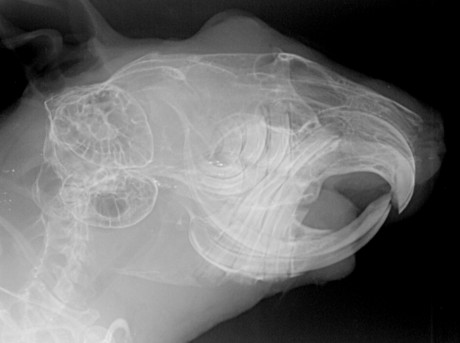

Röntgenbild Degu

Degu im digitalen Röntgen: Kopf von lateral